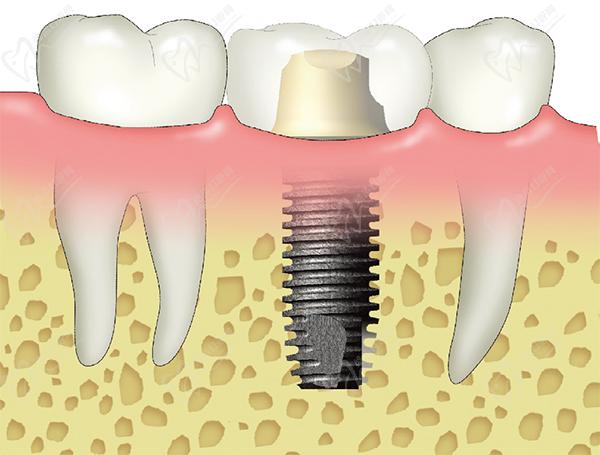

(1)口腔檢查:進(jìn)行詳細(xì)的數(shù)字化口腔檢查,包括拍攝全景X光片,以評估患者的牙槽骨情況、鄰牙情況以及軟組織情況。

(4)微創(chuàng)植入種植體:在局部麻醉下,利用Straumann導(dǎo)板手術(shù)器械實現(xiàn)高 效的外科手術(shù),并結(jié)合3D導(dǎo)板導(dǎo)航計算機種植系統(tǒng),通過微創(chuàng)手術(shù)將種植體植入牙槽骨中。

(1)生物學(xué)相容性:瑞士士卓曼種植牙的材料具有良好的生物學(xué)相容性,能夠與人體組織相容,減少不良反應(yīng)和免疫反應(yīng)。

(2)機械性能:瑞士士卓曼種植牙的機械性能優(yōu)良,能夠承受正常的咬合力和咀嚼力,具有良好的耐磨性和抗疲勞性。